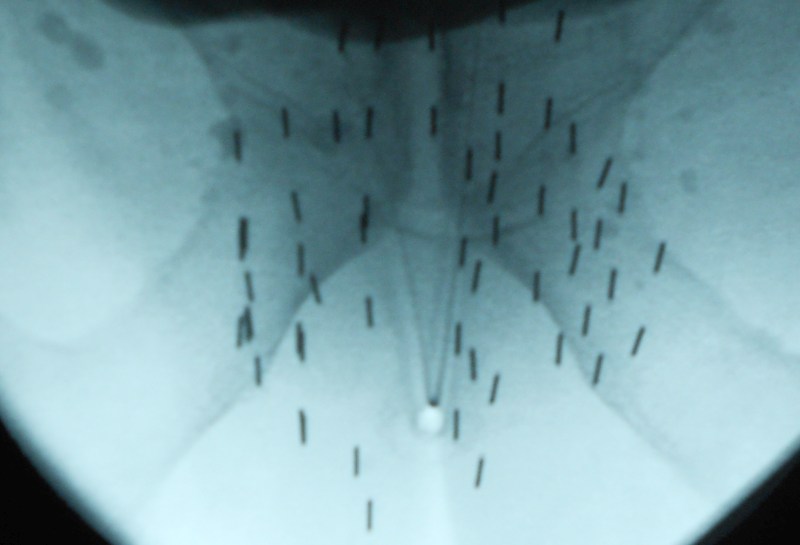

| Röntgenbild | Durchleuchtungsbild nach erfolgreicher Seeds - Implantation. |